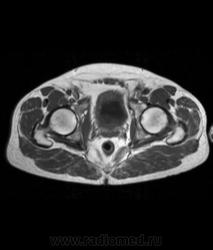

Для динамического контрастирования требуется инъектор, у нас с ним технические неполадки, поэтому контрастное вещество вводим от руки. Но в данном случае четко видно проростание опухолевого компонента через мышечный слой мочевого пузыря, даже некоторой инфильтрацией паравезикальной клетчатки. По гистологии плоско-клеточный рак. У пациента множественные метастазы в легких.